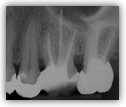

Bevor die Aufbereitung des Kanalsystems erfolgen

kann, ist es wichtig, die Länge des Wurzelkanals durch eine

Röntgenaufnahme exakt zu bestimmen. So wird verhindert, dass

Instrumente über die Wurzelspitze hinaus geschoben werden.

Bakterien könnten in das Knochengewebe verschleppt werden.